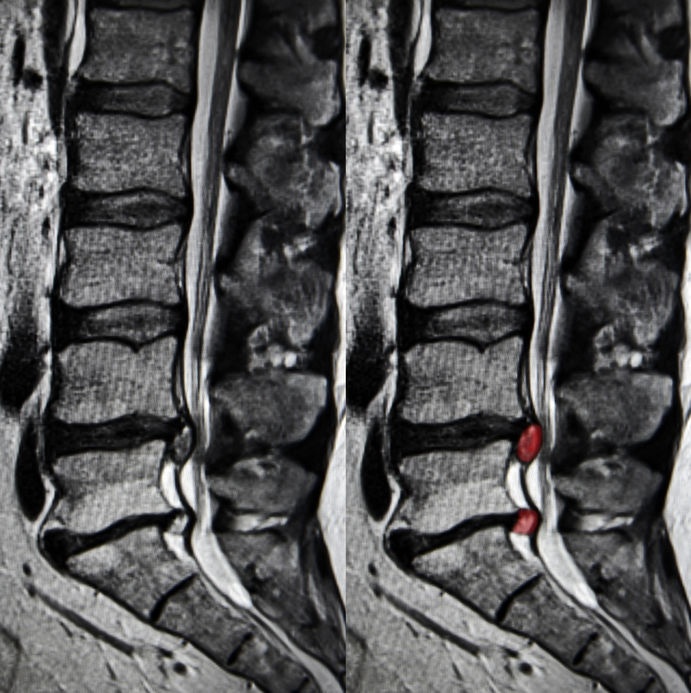

mri disc lumbar spine herniation back scan sciatica nerve colored sciatic

Gambar Menunjukkan Salah Satu Contoh MRI Scan Bagi Masalah Herniated

Gambar menunjukkan salah satu contoh MRI scan bagi masalah herniated www.pinterest.com

disc herniated slipped mri normal scan yang gambar rawatan bagi c5 dilihat menunjukkan perbezaan masalah diantara boleh contoh satu salah